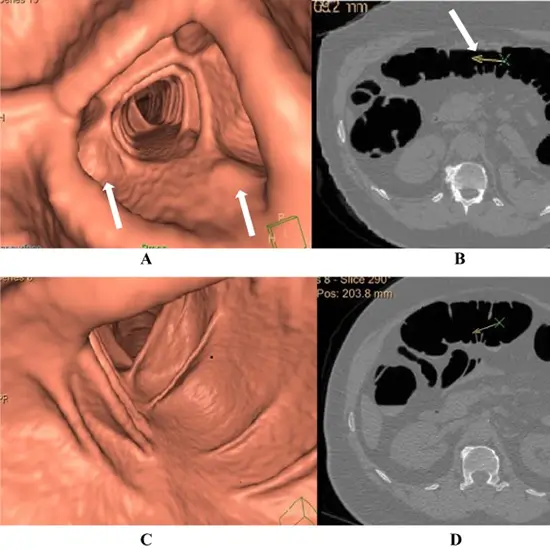

CT colonoscopy is also known as virtual colonoscopy and CT Colonography. It is a minimally invasive exam for screening for cancer of the large intestine. It obtains cross-sectional images of abdominal organs and combines them to provide a detailed view of the inside of the colon and rectum.